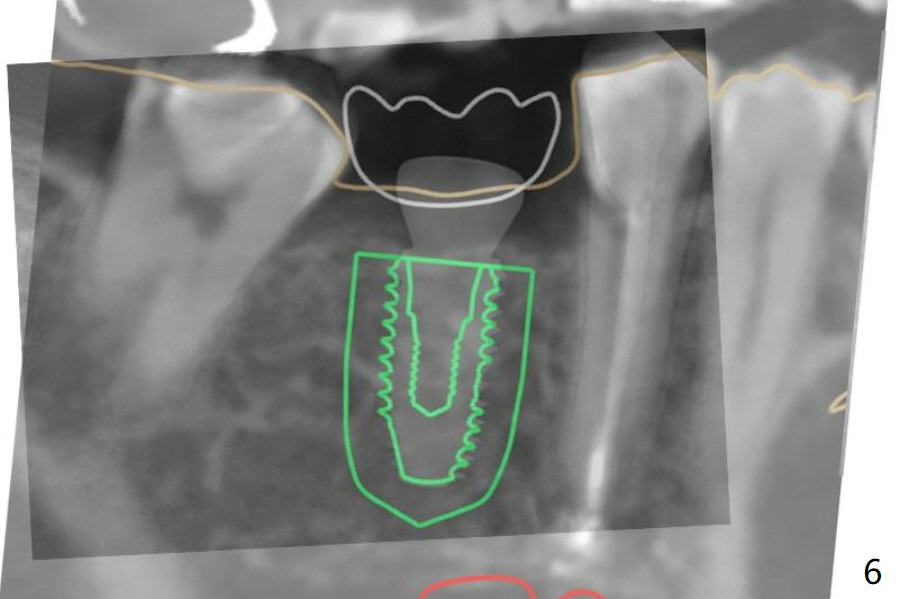

A 5x10 mm implant is placed at #30 with a surgical guide (Fig.1 *) in 10 minutes. The most amazing part of this surgery is that the guide allows you to place the implant at the precise level care-free (~ 1 mm subcrestal, Fig.2,3). Everything happens so quick that when a 5.5x3 mm healing abutment is placed (Fig.4), you are pleased to feel that the implant is stable (Fig.5). You could not ask for anymore. The fearful patient reports no postop pain. The implant is placed as planned (Fig.6, overlap image provided by the guide designer, Jennifer). The patient returns for impression nearly 2 months postop (Fig.7,8). It appears that the implant has osteointegrated without bone loss (Fig.7). The soft tissue is healthy around the just placed cementation abutment (Fig.8 (5.2x4(2) mm)). When the permanent crown is seated initially 2.5 months postop, the mesial contact is slightly tight and the occlusion is high. Bitewing shows the distal open margin (Fig.9 >). After mesial contact adjustment, the patient feels that the occlusion is better. With further occlusal adjustment, the crown is cemented without distal open margin (Fig.10). The patient returns to her home country for 3 months. The implant is doing well 3.5 months post cementation; impression is taken for #14 surgical guide.